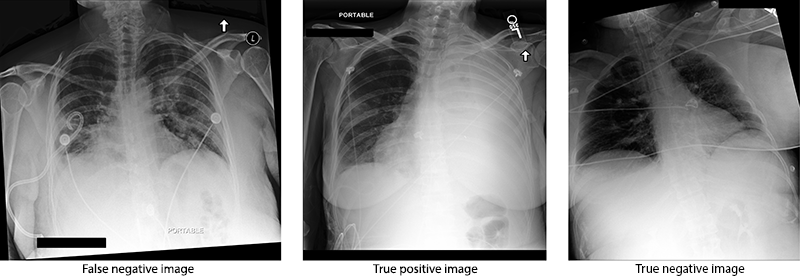

Figure 1: Pneumothorax detection - triplets

Few-Shot Learning on label limited datasets in medical imaging is not new Prabhu et al. (2019); Medela et al. (2019); Paul et al. (2021b). In our proposed approach, we work with limited data and inter-annotator differences. We evaluate our approach using the CheXpert Irvin et al. (2019) Chest X-rays dataset. Our approach of blending an FSL algorithm with image triplets, which we call Triplet Few-Shot Learning (TFSL), is practical and novel. Image Triplets is a set of three images - a false positive (FP) or false negative (FN) generated by the model, a true positive (TP), and a true negative (TN).

While collecting the training image triplets (Fig 1), a checking label is also collected. The checking label is -1 if the first image of the triplet is FN and 1 if the random image is an FP. The choice of -1 and 1 as labels is explained in Section 3.4. We tested sets of 50/100/150 image triplets and the fine-tuning model improved performance over the baseline model at 150 image triplets. The randomly selected 150 image triplets were used for training the TFSL algorithm, but all the failed inference images (except the ones that are used for training) were collected and used to validate the algorithm. False inference images are randomly selected from all the failed inference images.